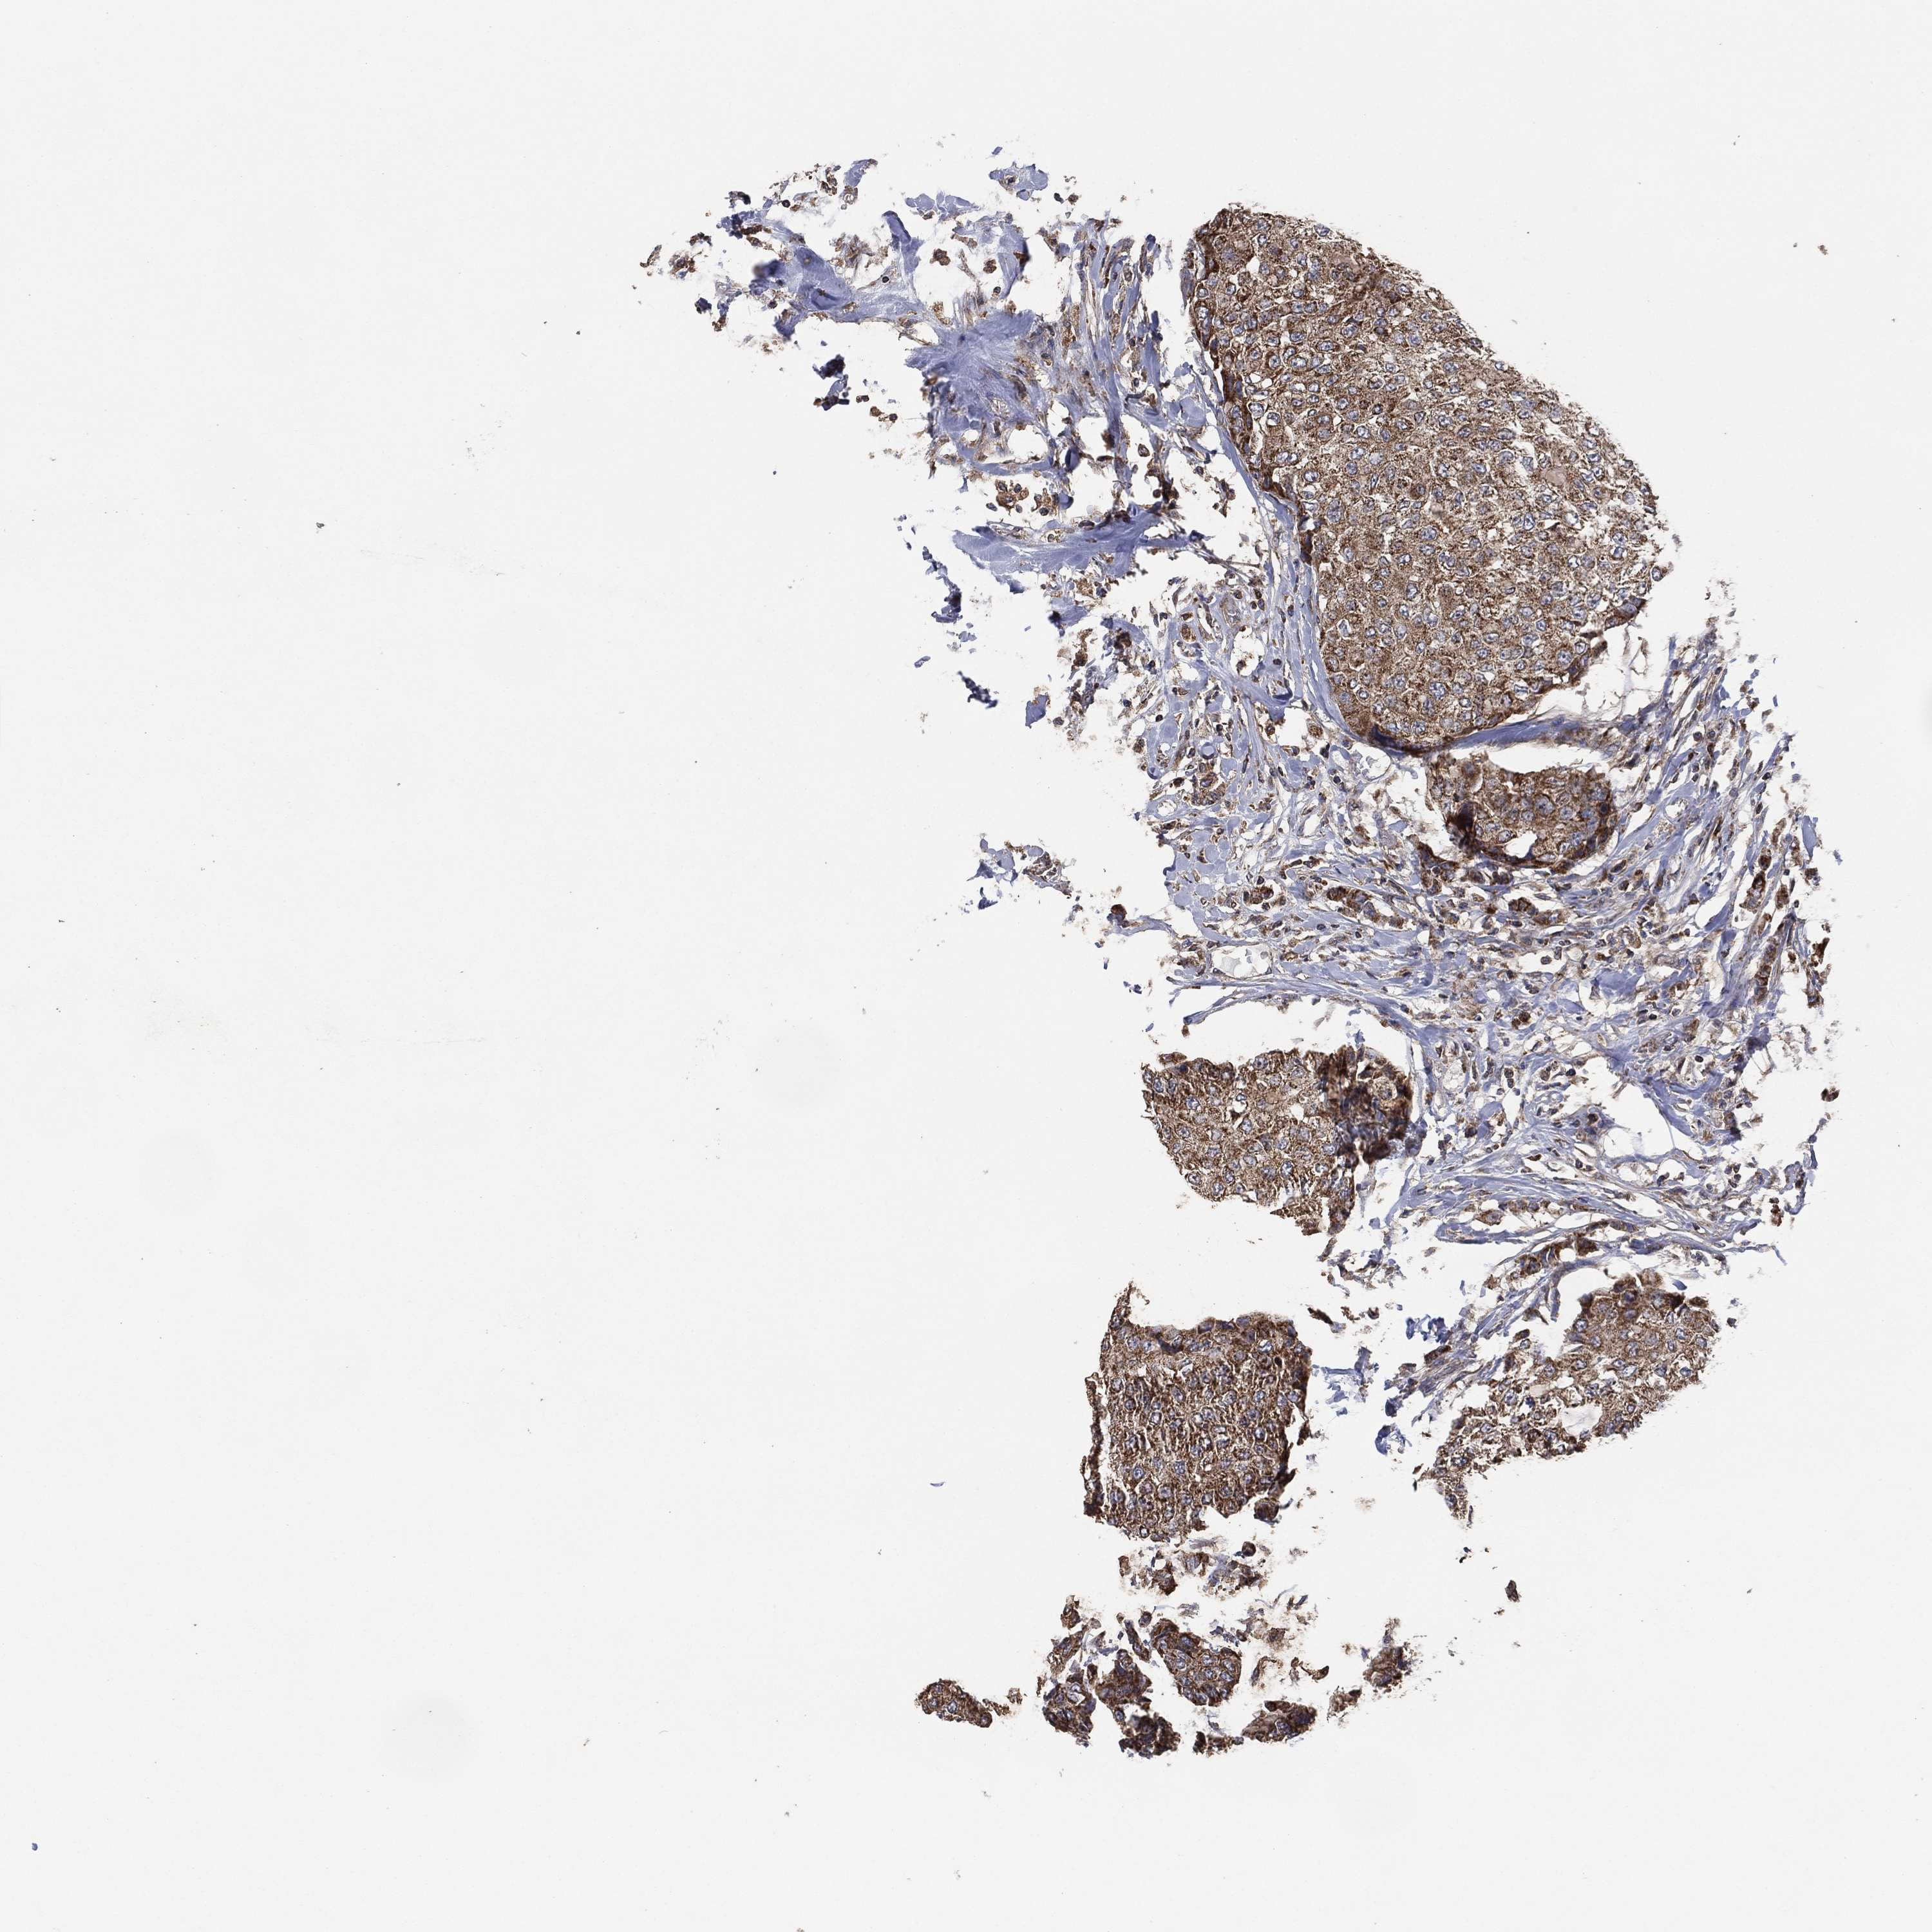

CANCER BREAST CANCER Show tissue menu

BRCA TCGA BRCA VALIDATION PROTEIN EXPRESSION